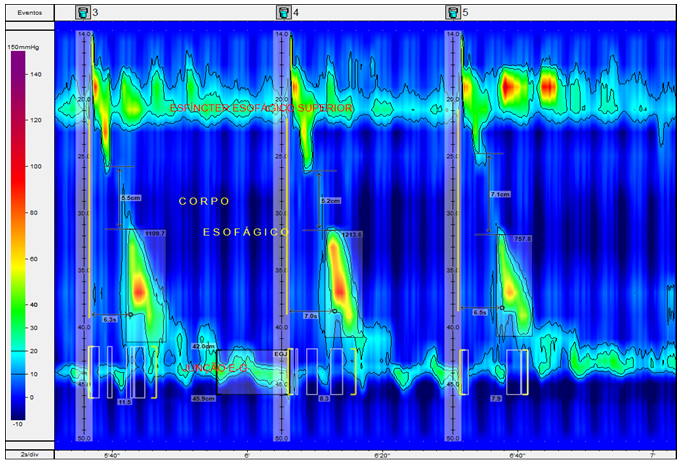

Manometria: Avalia a força e a coordenação dos músculos do esôfago ou do reto. É o exame que identifica por que a comida “trava” ou por que o refluxo acontece.